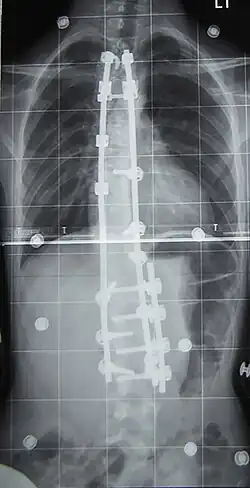

Preoperative (left) and postoperative (right) X-ray of a person with thoracic dextroscoliosis and lumbar levoscoliosis: The X-ray is usually projected anteroposterior, such that the right side of the subject is on the right side of the image; i.e., the subject is viewed from the rear (see left image; the right image is seen from the front). This projection is typically used by spine surgeons, as it is how surgeons see their patients when they are on the operating table (in the prone position). This is the opposite of many Chest radiographs, where the image is posteroanterior, i.e., projected as if looking at the patient from the front. The surgery was a fusion with instrumentation.